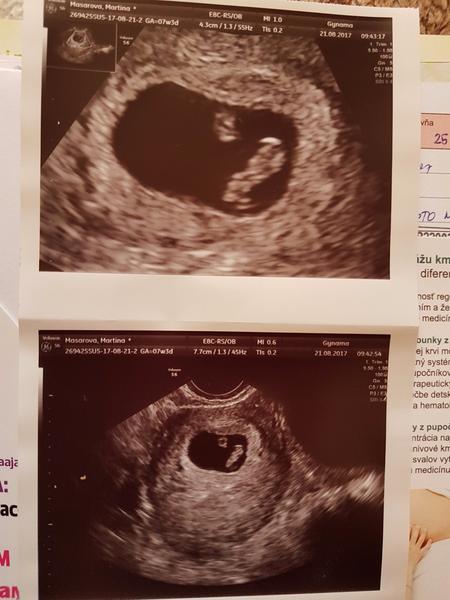

@martinkamm gratulujem k bábätku

@martinkamm gratulujem adam sa k tebe pridame k aprilovkam ;)

@cellesta mas krasne //